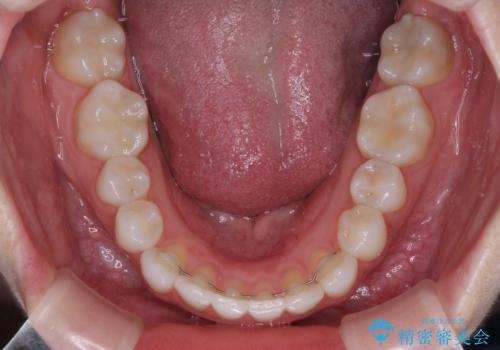

- 歯並びと虫歯をきれいにしたいとのことで来院された患者様です。

楽して短期間で歯列を整えたいとのことで、ワイヤー装置を用いて矯正治療を行い、矯正治療後に下顎の虫歯はセラミックインレー、上顎はPGAインレー(ゴールドインレー)、根管治療を行う歯についてはオールセラミッククラウンにて補綴治療を行うこととしました。

- 費用(概算)

矯正治療は8ヶ月ほどで終了し、速やかに虫歯治療に移行することができました。

保険治療で用いる樹脂(コンポジットレジン)で行った虫歯治療は、周辺が変色して汚くなっていましたが、下顎はセラミックインレーで審美的に、上顎はPGAインレーで歯に負担の少ない治療を行うことができました。